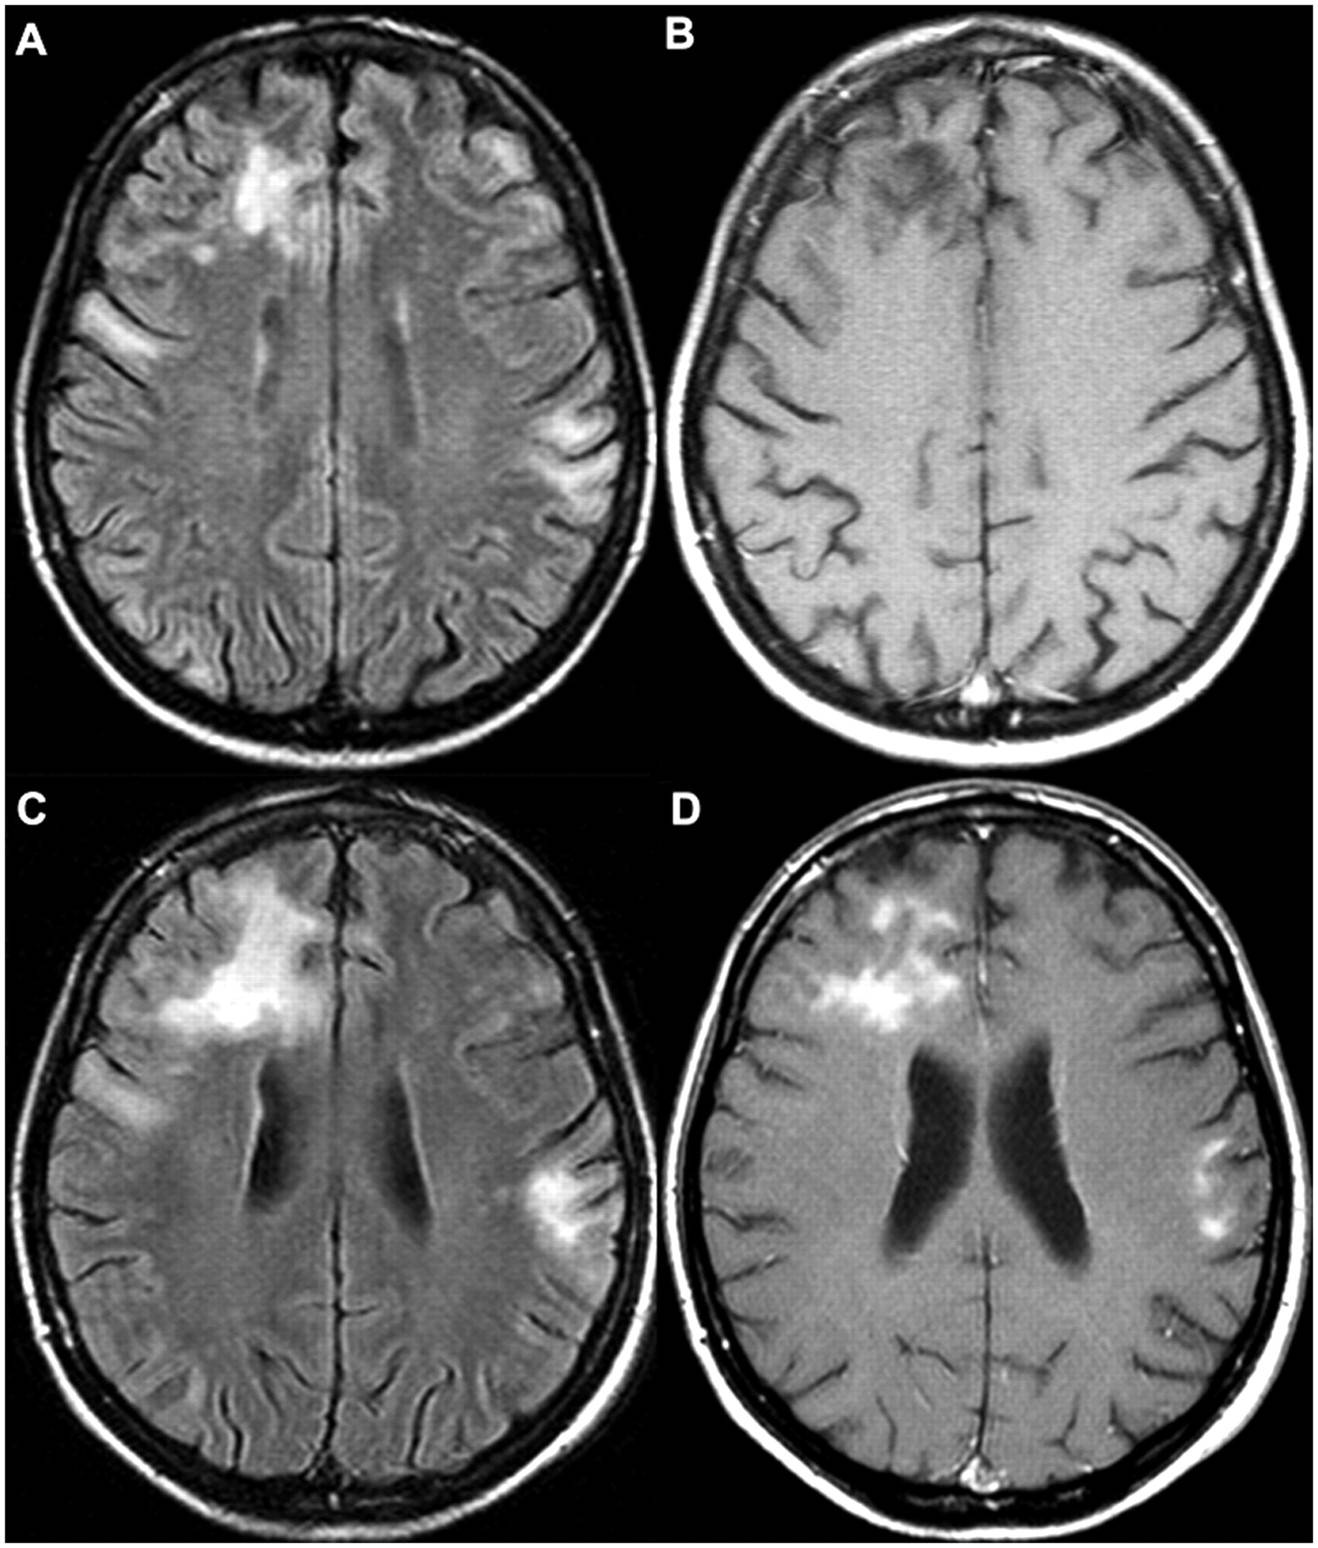

Fazekas grades. Инсульт на Dwi. Лейкоареоз Фазекас. Инсульт Dwi Flair несоответствие. Brain stroke MRI.

Fazekas grades. Инсульт на Dwi. Лейкоареоз Фазекас. Инсульт Dwi Flair несоответствие. Brain stroke MRI.